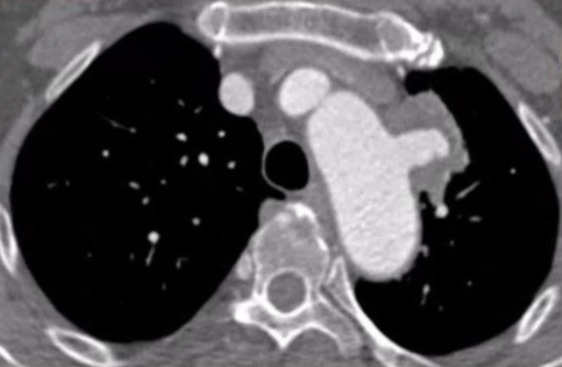

术前检查与评估

增强CTA显示,主动脉弓前壁假性动脉瘤深约2.23cm,基底宽约3.34cm。瘤体已累及左侧锁骨下动脉,且距左颈总动脉仅约4mm,距无名动脉约19.7mm。检查结果表明,该病例需要将覆膜区放置在无名动脉后,同时重建左锁骨下动脉和左颈总动脉,以恢复正常的血管通路,避免脑部供血不足等严重并发症的发生。

术后恢复情况

患者术后无神经系统定位体征,这意味着手术未对神经系统造成损伤,神经功能保持正常。术后五天复查CTA,可见假性动脉瘤瘤腔内已经完全血栓化,颈总动脉和锁骨下动脉分支血流通畅。出院前复查,LCCA与LSA分支形态良好,血流通畅,无狭窄,主动脉支架封闭效果好,无内漏,治疗效果令人满意。患者身体恢复良好,手术达到了预期治疗目标。

术前CTA

术后5天CTA